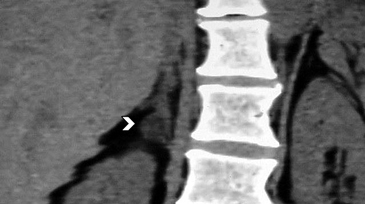

En la TC no contrastada las glándulas suprarrenales normales son homogéneas y simétricas, con una densidad muy similar a la del parénquima renal adyacente (Figura 1 a). Con un medio de contraste ev la glándula suprarrenal se opacifica en forma homogénea, similar al hígado o al bazo (Figura 1 b). Si la cantidad de tejido adiposo retroperitoneal es abundante las glándulas suprarrenales pueden aparecer enteramente rodeadas por grasa y su delimitación es más fácil (Figura 2 a); lo inverso ocurre en pacientes muy delgados con escasa grasa retroperitoneal (Figura 2 b). En RM, en secuencias ponderadas en T1 y T2 convencionales tienen una intensidad de señal homogénea, hipointensa respecto de la grasa adyacente e iso o hipointensa con respecto del parénquima hepático (Figura 3 a y b). En los cortes coronales se aprecia mejor la forma y la posición de las glándulas suprarrenales (Figura 3 c).

Figura 3. Glándula suprarrenal normal en resonancia magnética. (a) Cortes axial ponderado en T1 la señal de la glándula normal (flecha negra) es hipointensa respecto a la grasa retroperitoneal e isointensa respecto al parénquima hepático. (b) Cortes axial ponderado en T2 en que se muestra la glándula suprarrenal derecha (flecha blanca) y (c) corte coronal ponderado en T2 en que se muestra la glándula suprarrenal derecha (flecha blanca) y la glándula suprarrenal izquierda (flecha negra) con similares características de intendidad de señal. 3. Causas y prevalencia de las lesiones suprarrenales